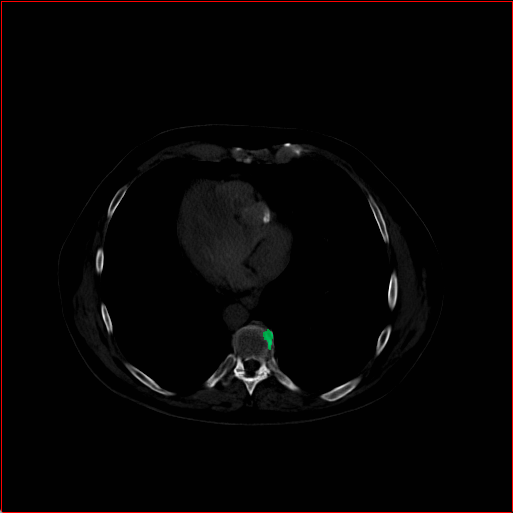

Panc. Tumor

1×1×11\times 1\times 1

mm

512×512×512512\times 512\times 512

Refer to caption

Figure 5: MAISI-v2 segmentation-guided results for five types of tumors. We show results for different voxel spacing and volume size to demonstrate the flexibility of MAISI-v2. Different Hounsfield Unit window is used to better show the contrast between tumor and normal tissues.